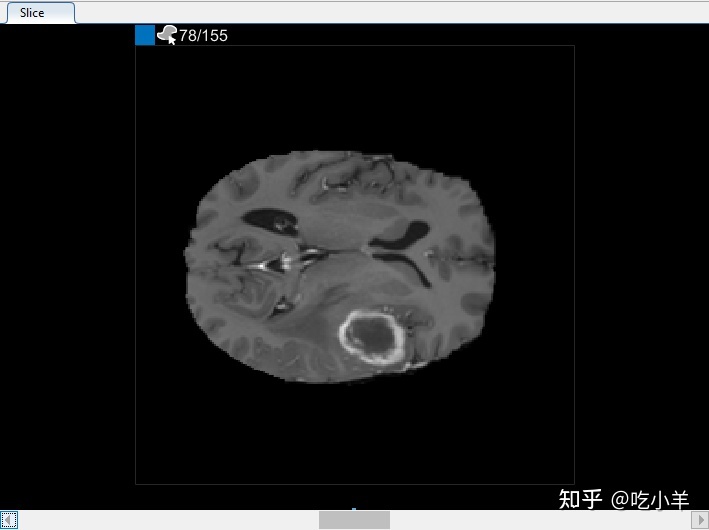

您还可以在“切片”窗格中查看体积的每个切片。使用窗格底部的滑块在切片之间移动。您可以在切片 35 到切片 88 上看到肿瘤。默认情况下,切片窗格显示沿 XY 轴定向的体积,但您可以使用分割器选项卡上工具条的方向部分中的按钮更改此设置。该切片窗格也是您使用绘图工具来定义的面具。

在切片窗格中,导航到对象第一次出现的切片,并开始使用绘图工具在每个切片上标记对象。在下图中,本示例使用画笔工具标记肿瘤。和以前一样,您可以在对象出现的每个切片上绘制对象,或者使用插值工具自动在多个切片上绘制。插值后,您可以使用绘图工具,例如橡皮擦,修改每个切片上的自动分割。